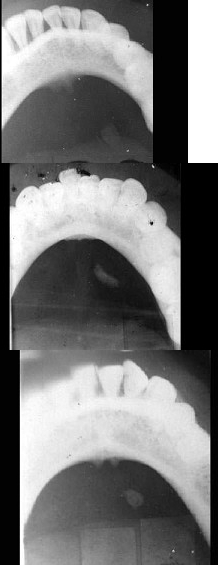

A.肺结核

男,55岁,左侧舌下肿胀不适2个月余,体检发现左侧舌下肿胀,舌下阜处可见脓苔黏附,触痛,按之可见淡黄色脓液从舌下阜溢出,摄片如图所示,最可能诊断()

A.左侧颌下腺涎石

B.左侧舌下腺涎石

C.左侧腮腺涎石

D.正常影像

E.左侧下颌骨含牙囊肿